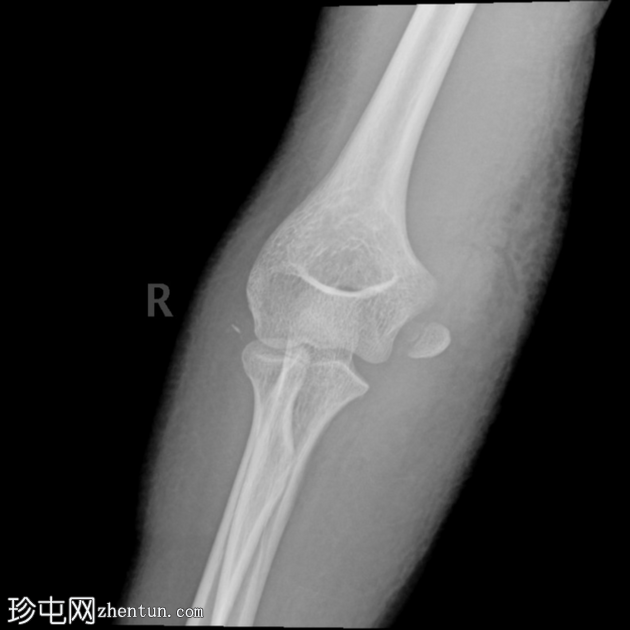

闭合复位后

X线片

3.png

正位片

4.png

侧位片

两个投照角度均显示肘关节复位良好。

复位后,骨碎片被明确识别为未完全骨化的内上髁骨折。

肘关节内仍有积液。